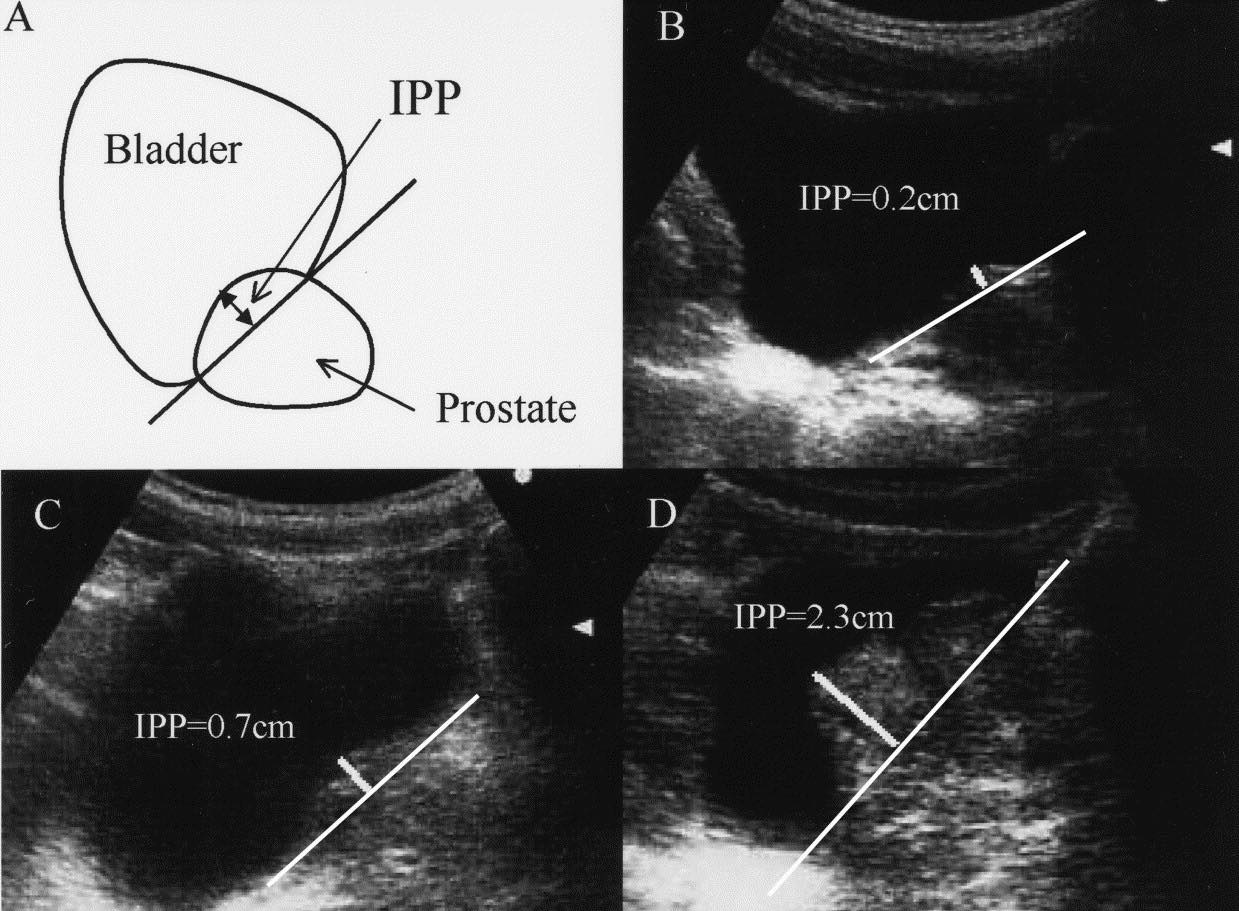

Hình ảnh này cho thấy các mức độ phì đại tuyến tiền liệt (BPH) trên siêu âm dựa trên thể tích tuyến tiền liệt và tình trạng lồi tuyến tiền liệt vào bàng quang (IPP):

Vì vậy, mức độ nghiêm trọng được xác định bởi cả thể tích tuyến tiền liệt và mức độ lồi vào bàng quang (IPP).